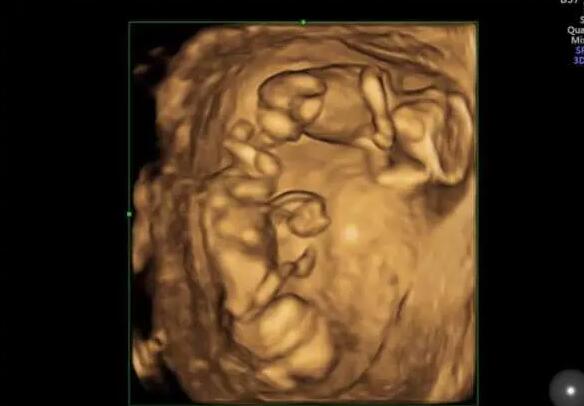

南京12345今日咨询热点,想咨询一下南京试管成功率高的私立医院有哪家?可以推荐一下吗?试管婴儿本是为了解决不孕问题而来,近些年在试管技术的帮助下也有万千家庭迎来了好孕,但是对于试管婴儿技术的利弊一直存在很多争议,甚至有一些做试管婴儿的朋友表示后悔了,下面就通过一个真实案例带大家了解真后悔做试管婴儿的背后原因。

南京12345今日咨询热点,想咨询一下南京试管成功率高的私立医院有哪家?可以推荐一下吗?

想咨询一下南京试管成功率高的私立医院有哪家?可以推荐一下吗?

如果你只考虑在私立医院做试管南京私立三代试管医院推荐我建议你选择家恩德运医院南京私立三代试管医院推荐,医疗团队专业南京私立三代试管医院推荐,环境也还不错。需要可以百度搜下。